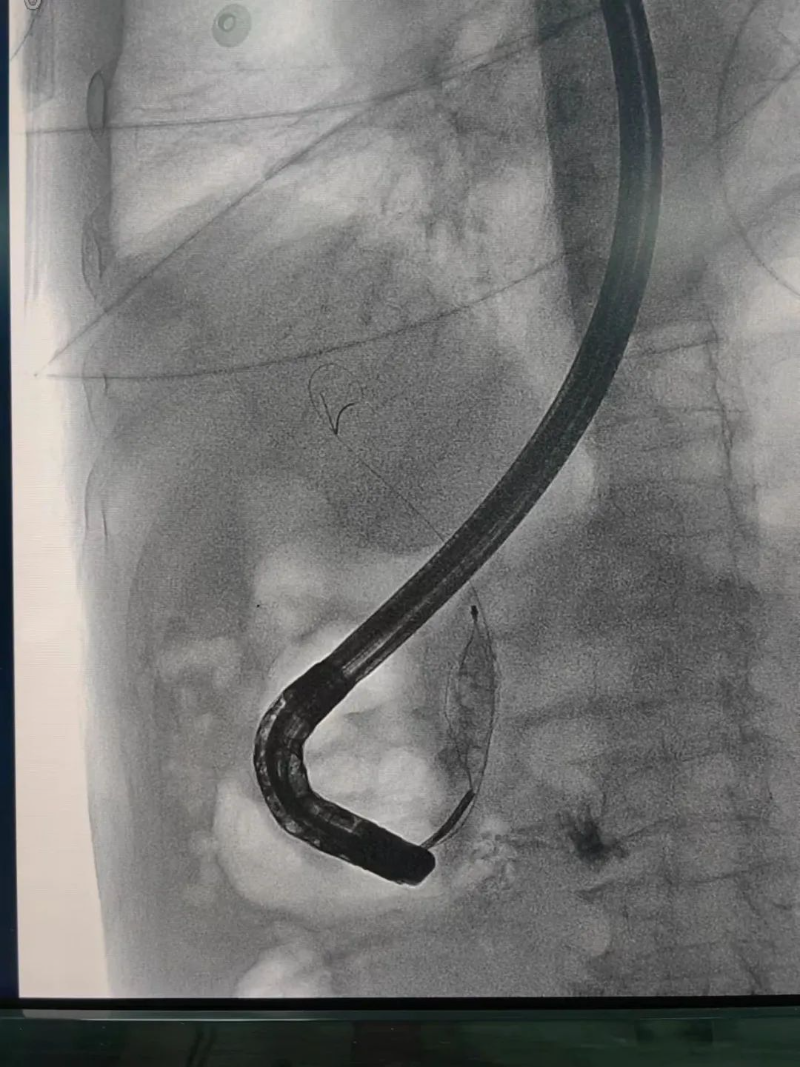

不開刀,膽中取石!揭秘神奇的ERCP

膽管結石、阻塞性黃疸、胰腺炎……這些疾病不僅讓人痛苦,還可能危及生命。過去,治療這類疾病往往需要開腹手術,創傷大、恢復慢。而現在,經內鏡逆行胰膽管造影術(ERCP) 作為一種先進的微創技術,已經成為膽胰疾病診斷和治療的重要手段。

它無需開刀,僅通過內鏡就能精準處理膽管和胰管的問題,大大減輕患者痛苦,縮短恢復時間。那么,ERCP究竟能解決哪些問題?它的優勢又在哪里?讓我們一起來了解。

什么是ERCP

經內鏡逆行胰膽管造影術(以下簡稱ERCP)是治療膽管結石的首選方法,ERCP屬于介入和微創手術,可以有效減少傳統手術對患者身體的創傷,能快速緩解臨床癥狀,降低相應并發癥的發生,改善肝功能,促進患者康復、減少圍術期應激,縮短住院時間,是項較安全、直觀、可靠的治療手段,對肝膽、胰疾病有較高的診斷和治療價值。

ERCP是經口內鏡膽道治療技術。是國際公認的膽管胰腺系統疾病診斷的金標準,是確診膽管結石的最佳方法。在ERCP基礎上,可以同時進行膽總管結石取石術、Oddis括約肌切開術、膽總管支架植入術、鼻膽汁引流術等微創手術,對膽總管結石等疾病進行安全、快速、有效的治療。